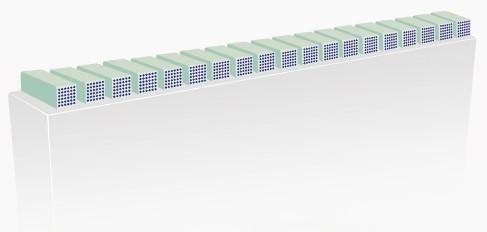

ComboWave трансдюсер с 3T технология

В сравнение с традиционните трансдюсери, ComboWave използват нов тип композитен пиезоелектричен материал за значително оптимизиране на акустичния спектър и намаляване на акустичния импеданс. Интегрирани с уникалната 3T технология на Mindray Animal Care, сензорите ComboWave осигуряват несравнима производителност с изключителна разделителна способност и еднородност на изображението.

Традиционен кристал

Композитен кристал

ComboWave

(композитен кристал с 3T)

1. лещи

2. 3 шумопоглъщащи слоя

3. композитен кристал

4. основен материал

ComboWave Transducer with 3T Technology

Compared to traditional transducers, ComboWave uses a new type of composite piezoelectric material to significantly optimize the acoustic spectrum and reduce acoustic impedance. Further integrated with Mindray Animal Medical's unique 3T technology, the ComboWave transducers allow you to experience outstanding performance with extreme image resolution and uniformity.

Traditional crystal

Composite crystal

ComboWave

(Composite crytal with 3T technology)

1. Lens

2. 3 Matching layers

3. Composite crytal

4. Backing material